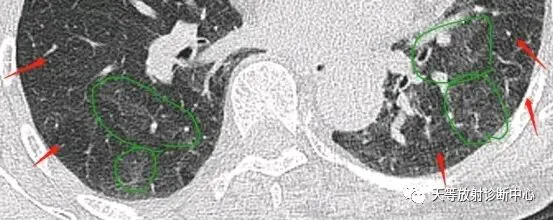

图2呼气状态:肺灌注不足,马赛克伪影,绿色区域出现类似磨玻璃影,HRCT尤其明显。

“马赛克”衰减征象在 HRCT上由两部分组成,即补丁状的异常透光区与斑片状的磨玻璃密度影。异常透光区主要为小气道狭窄所致局限性气体滞留引起,而磨玻璃密度影可为相对正常肺组织,也可为病变肺组织的表现。在以间质为主的病变中,磨玻璃密度影是间质纤维化形成或肺泡炎的表现;在以肺实质为主的病变中,磨玻璃密度影反映了肺气腔的不完全填充,肺泡腔内可有出血、炎性 渗出、蛋白成分等;慢性阻塞性肺疾病中,磨玻璃密度影反映了局部血流量的增加,可见到病变区域肺动脉增粗。

“马赛克”衰减表现为补丁状的异常透光区与斑片状的磨玻璃密度影镶嵌存在,对各类疾病无特征性,但在分布、形态及伴随征象等方面有一些特点。1、以间质为主的病变中,“马赛克”衰减多分布于肺的周边部位、胸膜下或沿支气管血管束分布,边界多模 糊。2、以肺实质为主的病变中,“马赛克”衰减多表现为弥漫性分布;呈斑片状或小叶、肺亚段分布的“马赛克”衰减,多见于慢性阻塞性肺疾病。